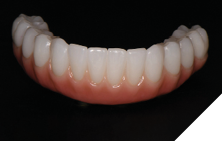

The patient returned 2 weeks from the impressioning appointment for a prototype try in. At this appointment the esthetics, phonetics, soft tissue approximation and occlusion were confirmed. There was no requirement for a verification jig due to the accuracy of the Nexus solution. The restorations were manufactured with milled gold anodized titanium bars overlaid with monolithic zirconia (Figs. 24A-C, 25A-C).

Fig. 24A

Fig. 24B

Fig. 24C